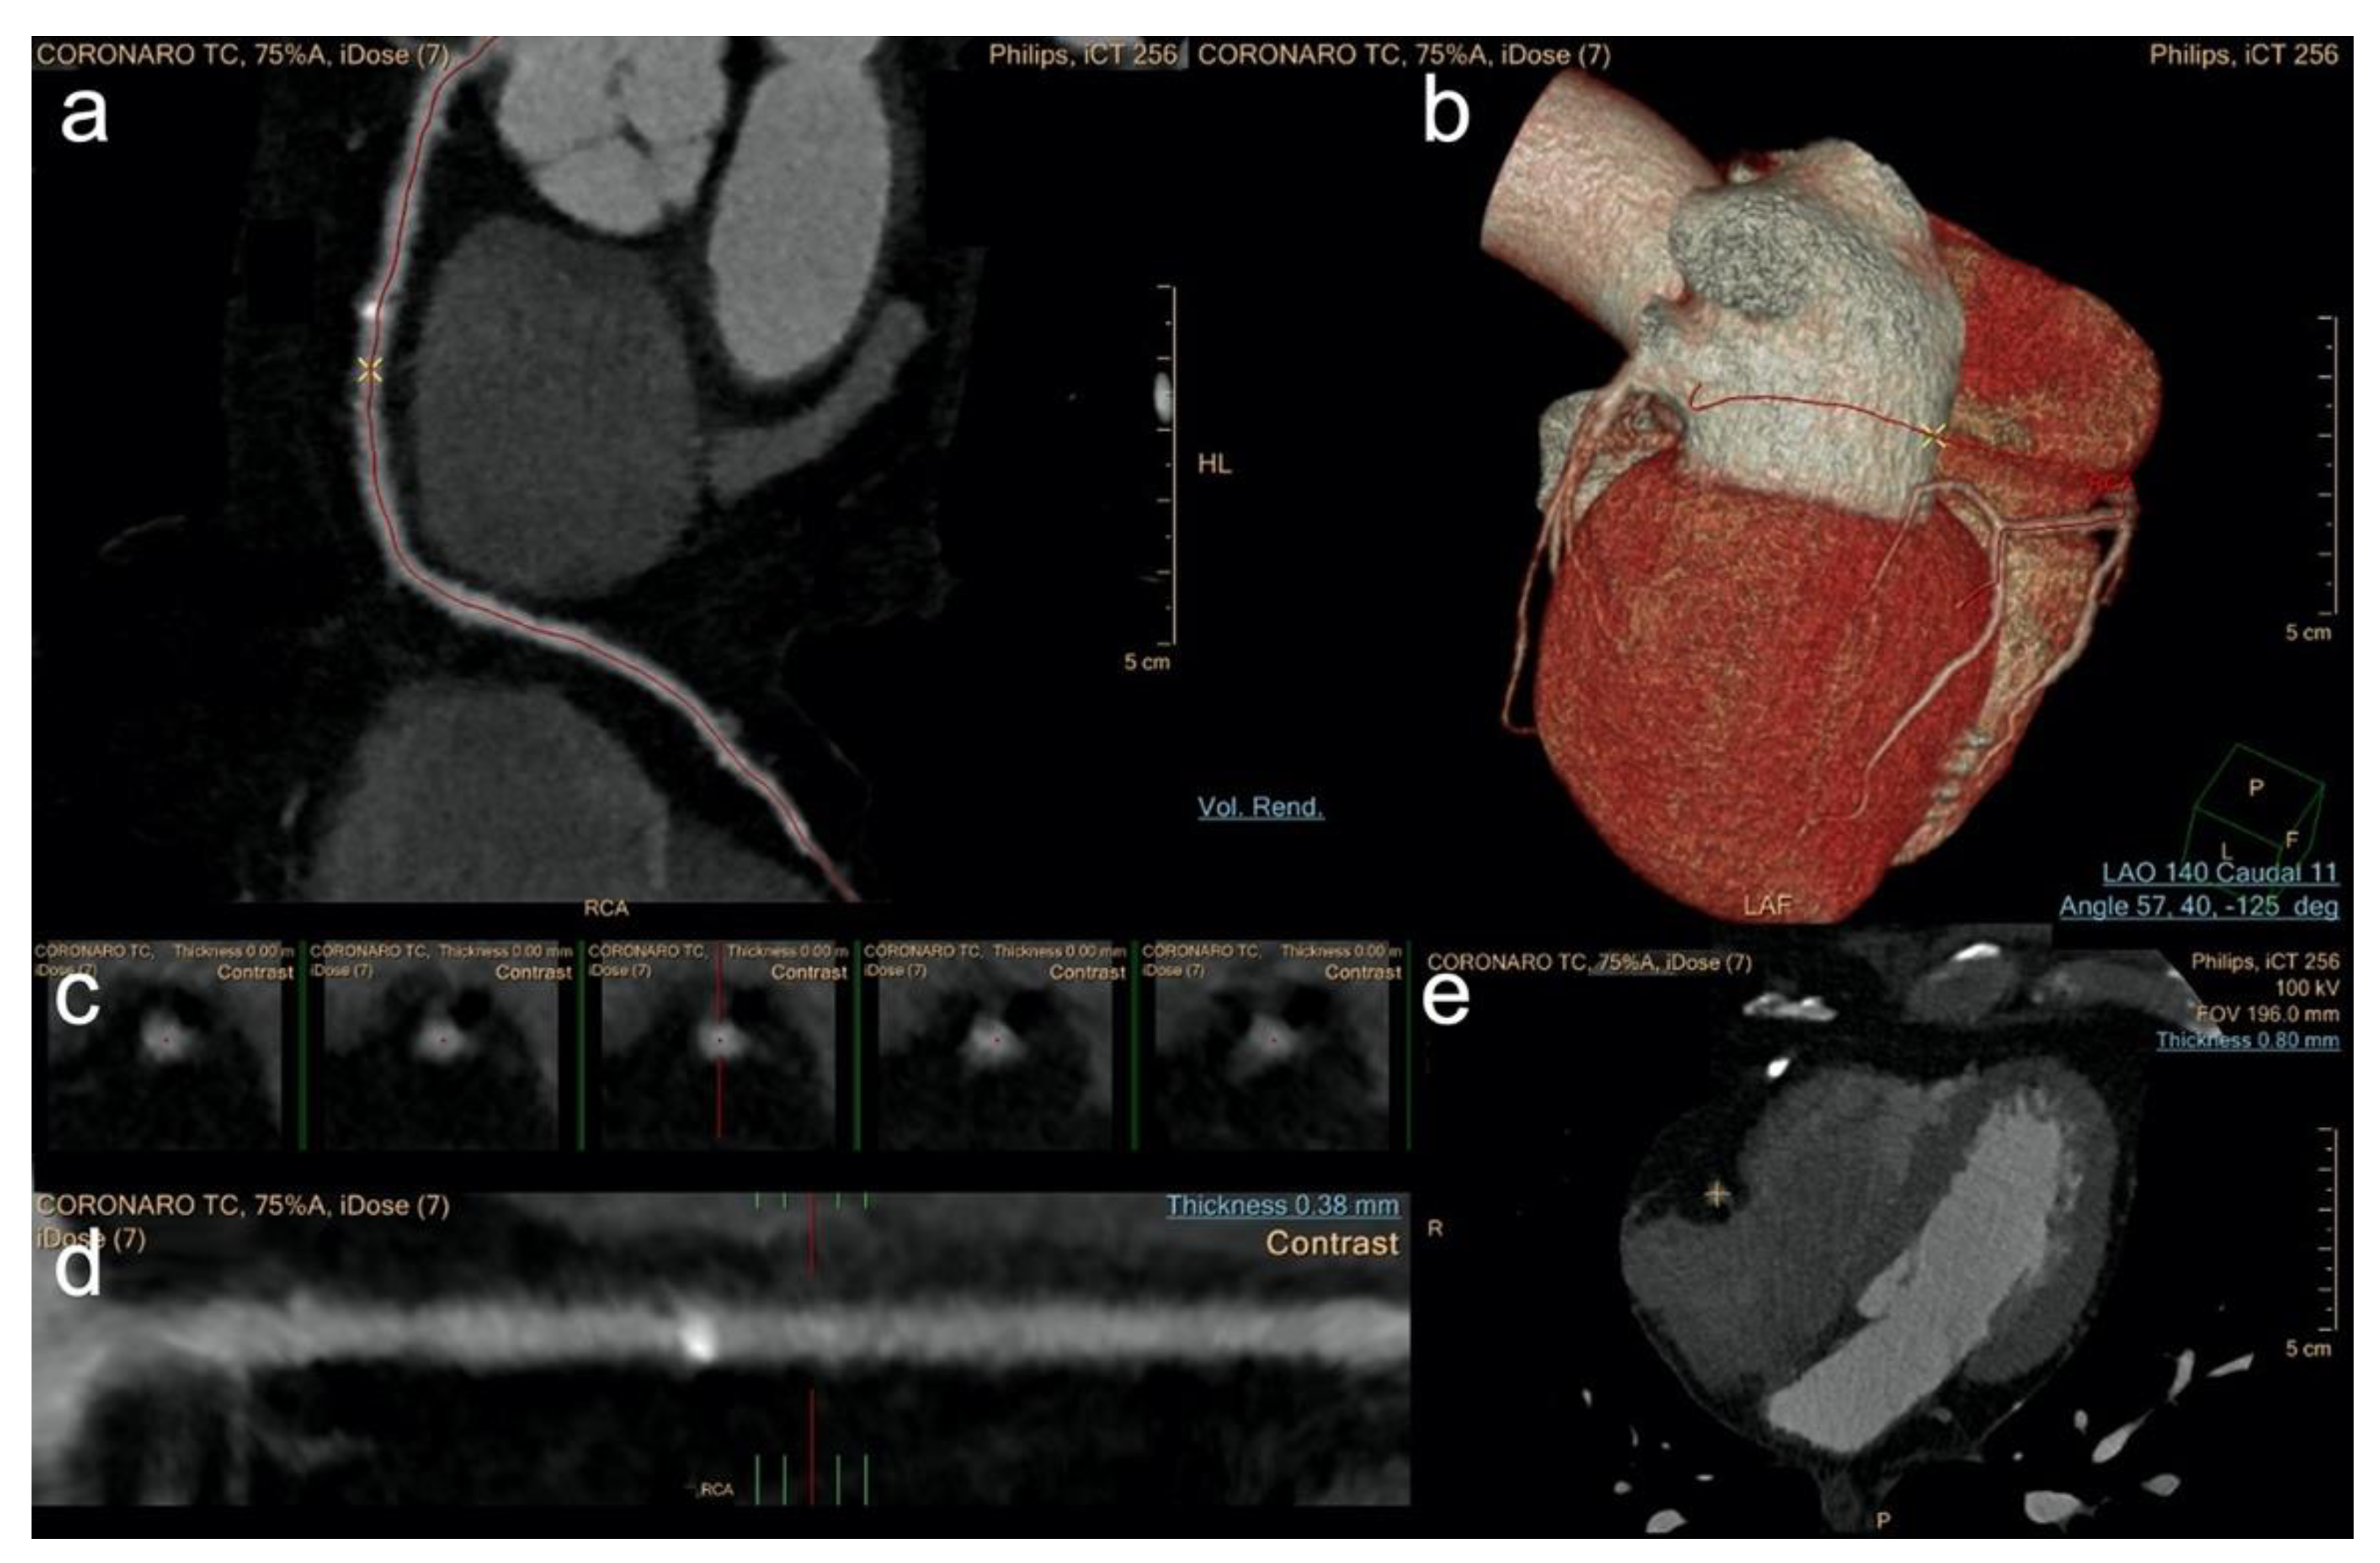

2.3. Image Post Processing—Group 1

2.5. Image Post Processing—Group 2